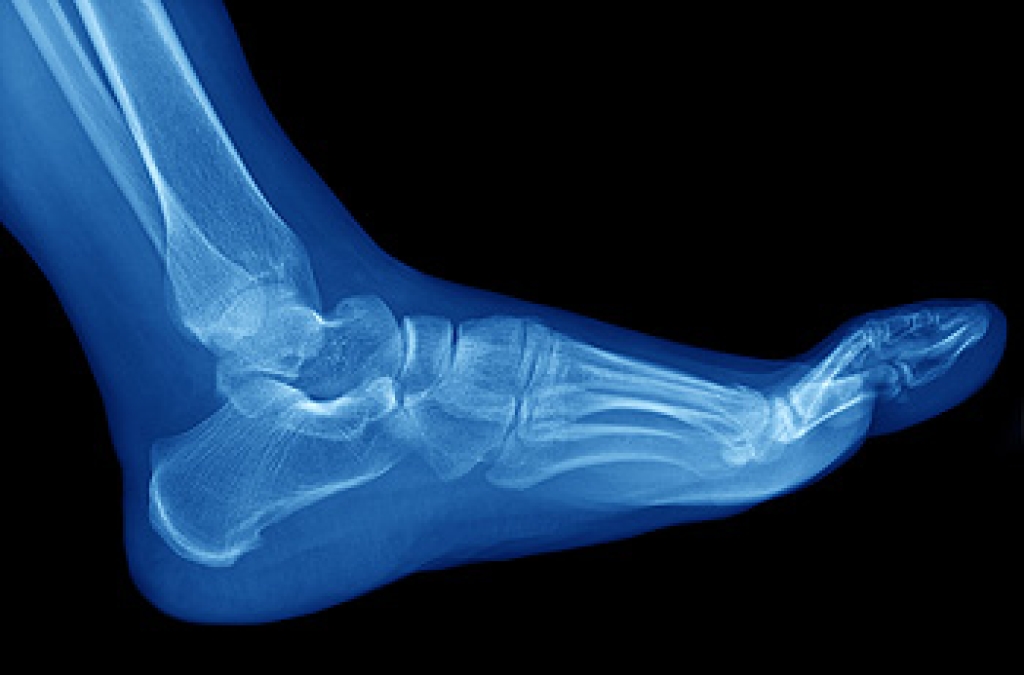

Neuropathy is a condition that leads to damage to the nerves in the body. Peripheral neuropathy, or neuropathy that affects your peripheral nervous system, usually occurs in the feet. Neuropathy can be triggered by a number of different causes. Such causes include diabetes, infections, cancers, disorders, and toxic substances.